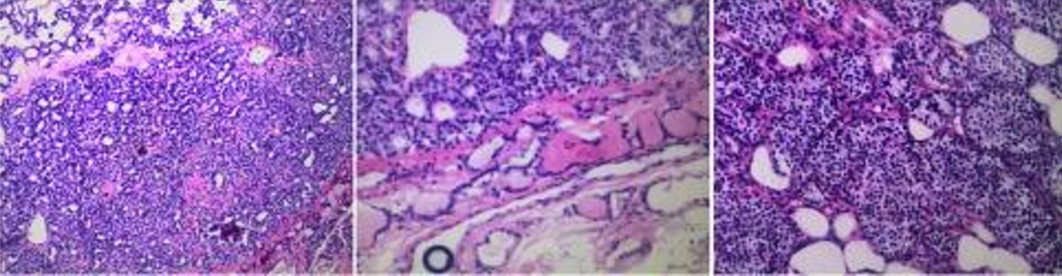

患者被诊断为pHPT,接受利尿剂治疗并切除甲状腺右下的肿物。术中快速冷冻切片显示有甲状腺腺瘤结节的可能。同时,术中PTH水平没有明显下降。考虑到冷冻切片分析和术中PTH测量并不能明确最终诊断,进一步的颈部探查会造成不必要的额外损伤并延长手术时间,在与家人沟通后终止了手术。术后病理检查提示甲状腺滤泡腺瘤,伴有少量甲状旁腺组织(图2)。

图2 第一次术后病理